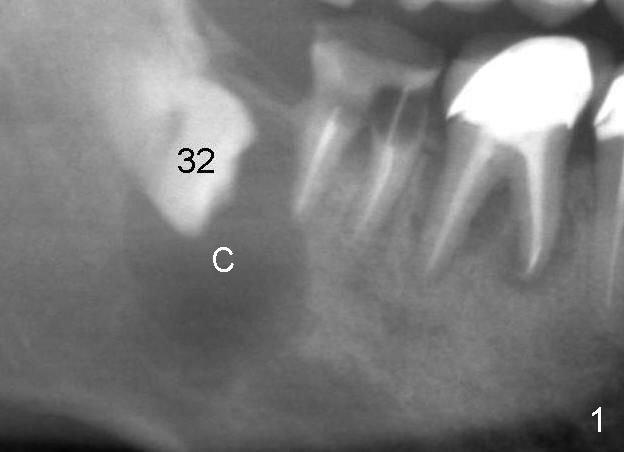

A 47-year-old man has poor dentition (Fig.1).  The tooth #31 is non salvageable.  It has two roots.  There is a dentigerous cyst (C) associated with #32.  There is no apparent bone distal to the distal root of the 2nd molar.